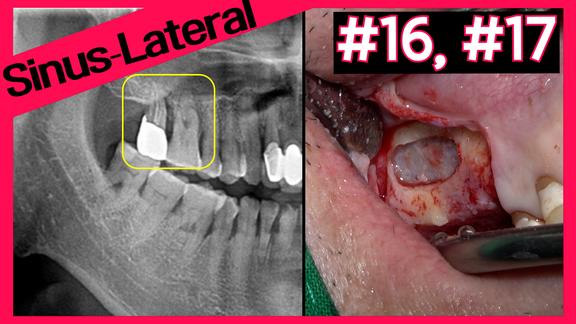

Implant Placement with Sinus Graft

온라인서저리

2024-04-23T00:00